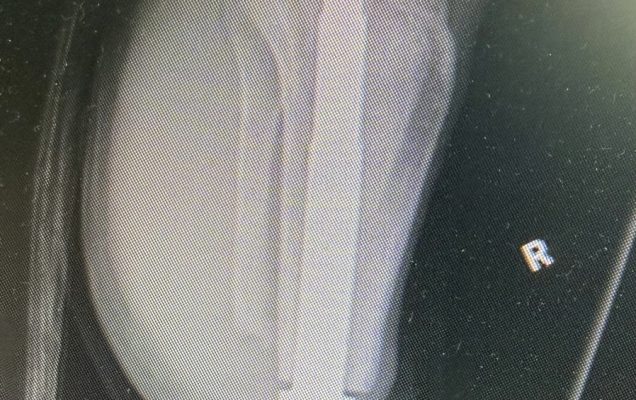

Osseointegracja polega na trwałym połączeniu implantu z kością, co umożliwia bezpośrednie mocowanie protezy bez konieczności stosowania tradycyjnego leja protezowego. Rozwiązanie to zapewnia pacjentom większy komfort użytkowania, lepszą kontrolę ruchu oraz wyraźną poprawę jakości życia. Przeprowadzona operacja była szczególnie wymagająca, ponieważ objęła obie kończyny jednocześnie. Jednoczasowe wykonanie zabiegu niesie jednak istotne korzyści – pozwala uniknąć drugiej hospitalizacji i kolejnego znieczulenia ogólnego, skraca całkowity czas leczenia oraz umożliwia prowadzenie symetrycznej rehabilitacji obu kończyn już od początku procesu usprawniania. Dzięki temu pacjent ma szansę szybciej powrócić do samodzielnego funkcjonowania.

Tego typu zabiegi należą do rzadkości i są wykonywane jedynie w nielicznych, wysoko wyspecjalizowanych ośrodkach. Operacje osseointegracji stanowią ważny krok w kierunku przywracania sprawności i niezależności osobom, które doświadczyły ciężkich urazów.